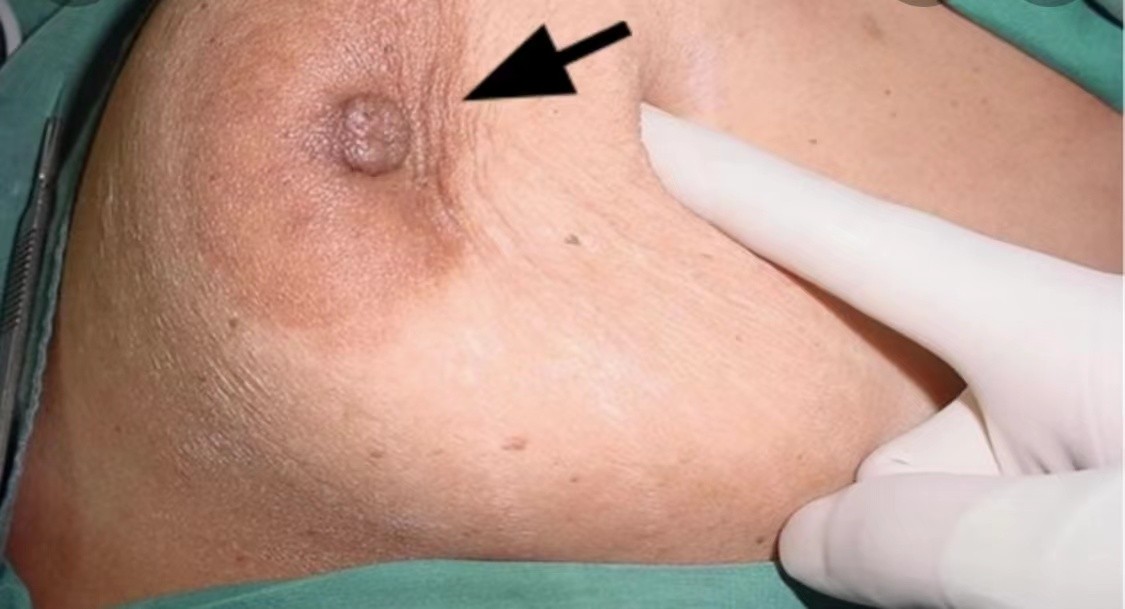

乳腺癌乳頭內陷圖

乳腺癌乳頭內陷